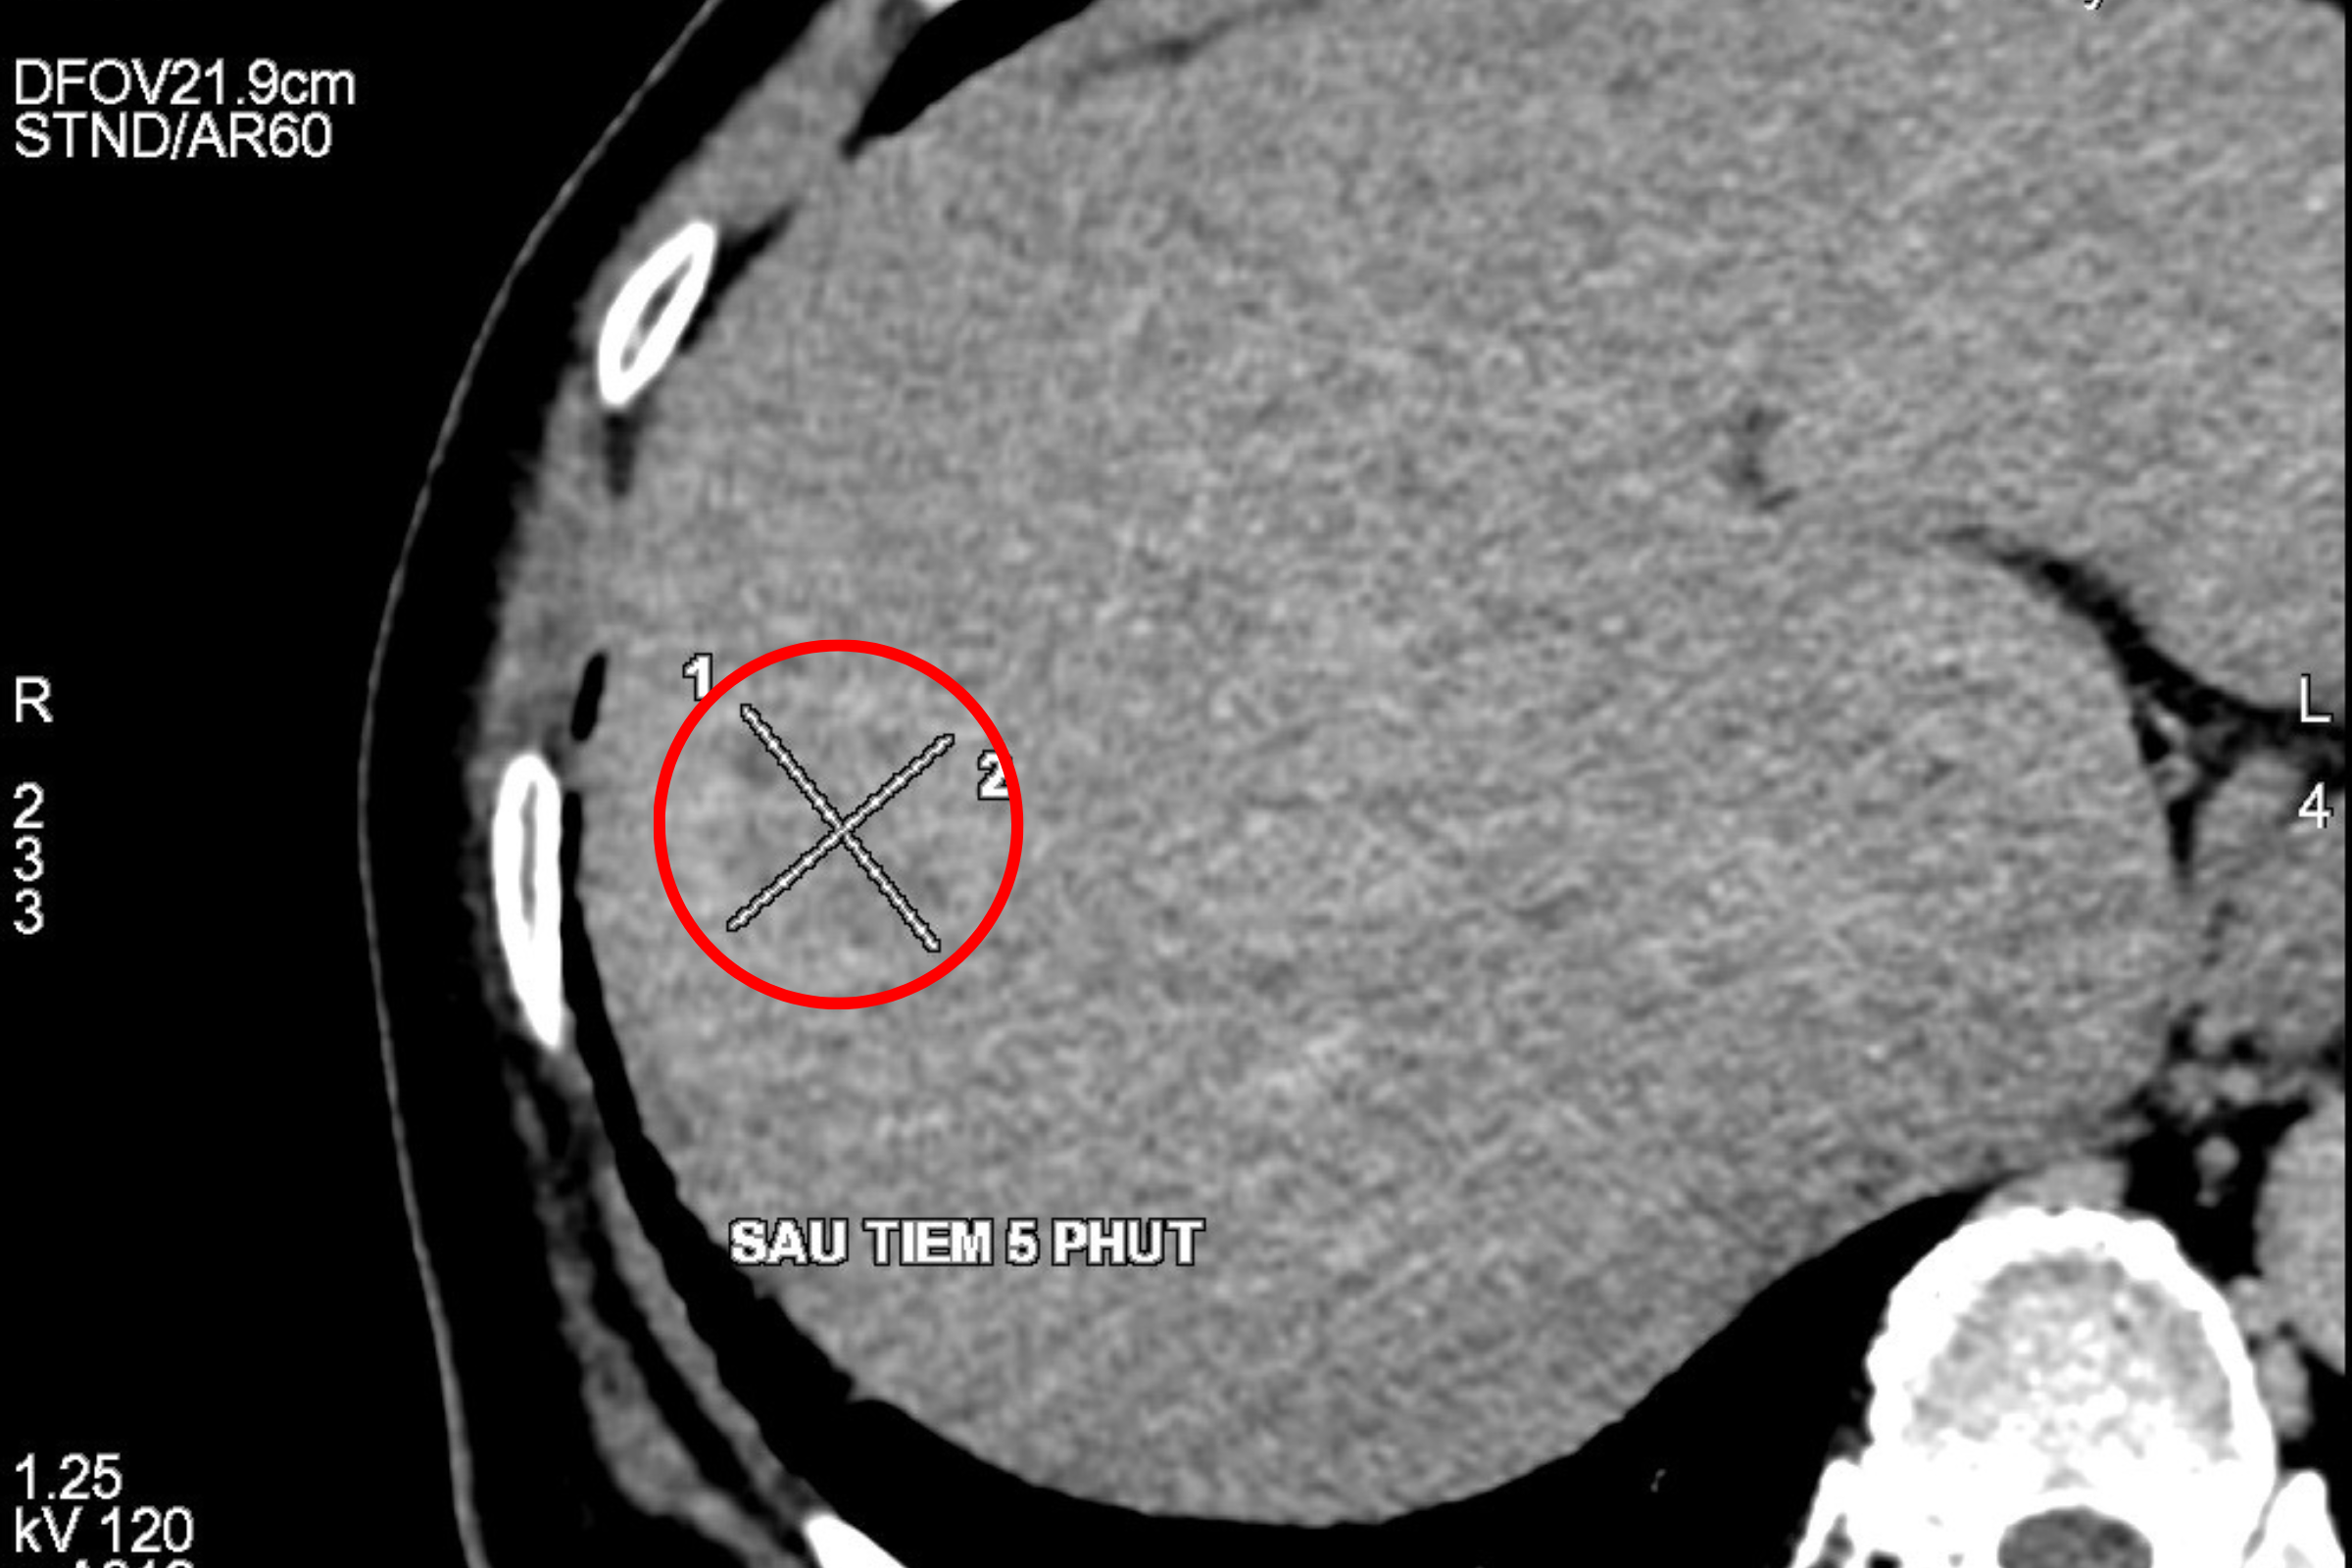

“Trên hình ảnh chụp CT 2560 lát cắt cho thấy, sau tiêm 25s thì động mạch ngấm thuốc cản quang vào khối u rất mạnh, thải thuốc nhanh ở thì tĩnh mạch cửa và thì muộn. Với đặc điểm huyết động học này thì bác sĩ hướng đến đây là một trường hợp ung thư biểu mô tế bào gan, kích thước nó vẫn còn khá nhỏ, khoảng 3cm và khu trú, chưa có các nốt di căn tại gan hay di các các cơ quan khác trong cơ thể.”

Dưới sự hướng dẫn của hình ảnh chụp CT 2560 lát cắt kết hợp siêu âm, ekip bác sĩ đã khoanh vùng chính xác vị trí khối u gan. Thông qua vết rạch nhỏ khoảng 3mm, bác sĩ đã đưa đầu kim đốt sóng cao tần đơn cực tiếp cận u gan, sử dụng sóng cao tần loại bỏ khối u.

“Khối u của bệnh nhân T nằm ở vị trí rất cao, gần sát vòm hoành, gây khó khăn trong việc quan sát và xác định chính xác vị trí khối u. Tuy nhiên, Công nghệ CT 2560 lát cắt đã phát huy tác dụng ở tình huống này, dưới hướng dẫn của máy chụp CT 2560 lát cắt, cung cấp hình ảnh 3D độ phân giải cao đã giúp các bác sĩ nhanh chóng tiếp cận và xử lý khối u thuận lợi, rút ngắn thời gian can thiệp.”